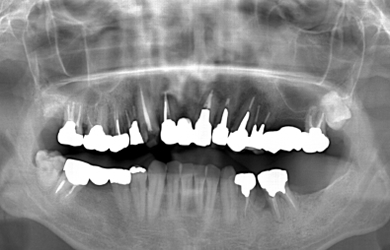

骨再生インプラント治療+セラミック治療

| カテゴリー | 【インプラント治療】【セラミック治療】 | ||||||||||||||||||||||||||||||||

| 性別/年齢 | 男性 / 50歳 | ||||||||||||||||||||||||||||||||

| 主訴 | 現在ムシ歯になっている箇所と、痛みのある部分の治療をセラミックで行って欲しい。 | ||||||||||||||||||||||||||||||||

| 治療方針 | ソケットリフト法により上顎洞底部を挙上することにより、骨の無い部分に骨をつくってあげ、インプラント治療を可能にする。 | ||||||||||||||||||||||||||||||||

| 治療内容 | インプラント2本(ソケットリフト)、メタルボンドセラミック5本、ハイブリッドセラミック2本 | ||||||||||||||||||||||||||||||||

| 総治療費 | 1,355,300円 | ||||||||||||||||||||||||||||||||

| 治療期間 | 海外から9ヶ月 |